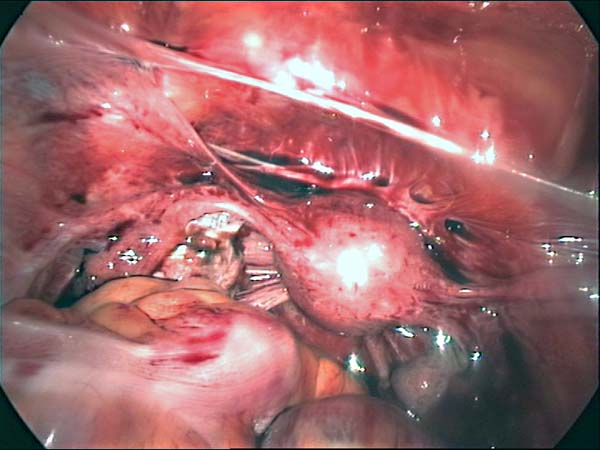

Laparoscopy Photos Ovarian Cyst Ovarian Cystectomy Uterine Septum Tubal Pregnancy